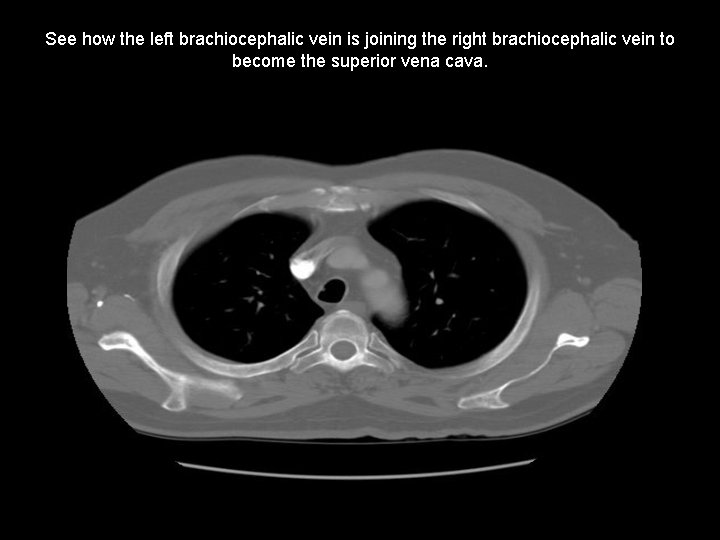

See how the left brachiocephalic vein is joining the right brachiocephalic vein to become the superior vena cava.

Contrast in the right brachiocephalic vein has been diluted by blood from the left brachiocephalic vein as they combine to form the SVC.